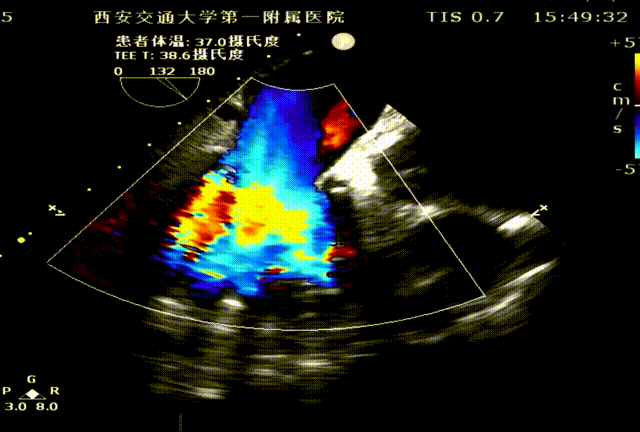

台上复查食道超声,瓣架圆形展开,启闭良好: